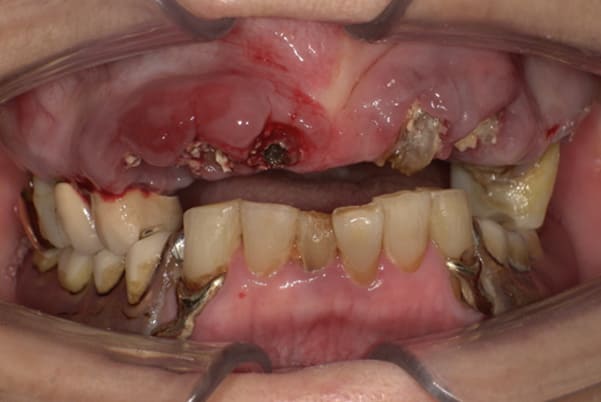

上前歯はブリッジの差し歯により根が折れ炎症を起こしお痛みのある状態でした。

原因は長期使用により下の義歯の歯が削れたことにより、下前歯が上前歯を突き上げ強い力が加わっていたことが根本的な原因と考えられます。

治療前は、奥歯が下がり、かみ合わせが乱れています。適切な入れ歯はそのままのかみ合わせで義歯を作るのではなく治療後のように、前歯から奥歯までのラインが真っすぐ揃った、かみ合わせの面を適切に付与し、よく咬め、残りの歯に負担がかからないかみ合わせとしました。

とにかく何も食べられないこと、人に会えないことから、なるべく早く何とかしたいとのご希望でした。

患者様とご相談の上、まず早急に上記を回復させるため、初診含め3度の来院でお食事ができ、見た目を回復できるように治療用義歯を作製、装着しました。

本来は、数本の上前歯の折れてしまって残せない歯は抜いてから歯肉の治癒を待ち、数か月後に型どりから作製になりますが、抜歯即時義歯といって、歯を抜く前に型、かみ合わせをとり、抜歯を行ったその日に上下の義歯を装着する特殊な治療法を用いたことで、10日後には治療用義歯をお口に装着することができ、お痛みもなくお食事ができ、ご友人とのお食事にも行けることが可能になりました。

本来、入れ歯作製は技工所と言って、義歯を作製する所に発送するため、作製には時間がかかりますが、院内に技工専用スペースを完備しており、長年、義歯治療において、技工も技術の習得してきましたので技工士さんではなく、かみ合わせの道具も私自身で院内で作製したことで、初診日の次の日にご来院いただきかみ合わせを採ることで、診断、型どり、かみ合わせ、装着まで10日という最短のご希望にこたえらた方です。

お写真は治療用の仮の入れですが普段通りお食事ができるとのことで少し食べ物もついています。。。

上顎治療前

上顎治療後

根のみの7本は虫歯にもなっており歯肉は腫れあがっています。

残りの歯もレントゲンで重度の歯周炎によりぐらぐらな状態でした。

下顎治療前

下顎治療後

治療前の入れ歯の奥歯は、治療後の義歯と比較しても分かるように、歯が削れ平らになった状態です。

これにより奥歯のかみ合わせは低くなり、前歯のみが強くあたり、かみ合わせにより上の前歯大きな負担がかかっていたことにより、上の前歯が折れたことが考えられます。